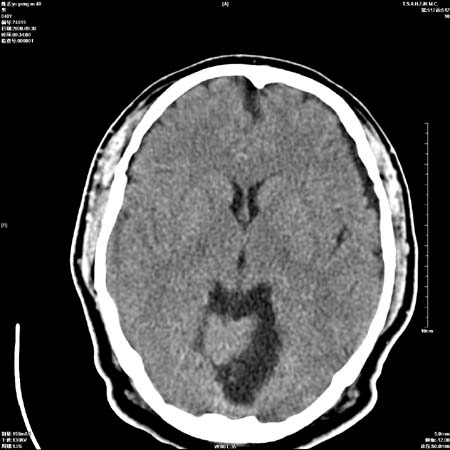

以下是引用zjzjr在2008-10-4 20:29:00的发言:[br]右颞叶皮质区密度略减低,脑沟较对侧变浅,考虑早期脑梗塞,建议mri.左侧小脑幕缘旁可见带状低密度影,轻度占位效应,支持蛛网膜囊肿,枕大池区亦考虑蛛网膜囊肿.

以下是引用流浪星在2008-10-4 20:06:00的发言:[br]大脑大静脉池增宽,脑萎缩引起,目前的ct表现不能解释临床症状,建议短期复查或做mr检查。